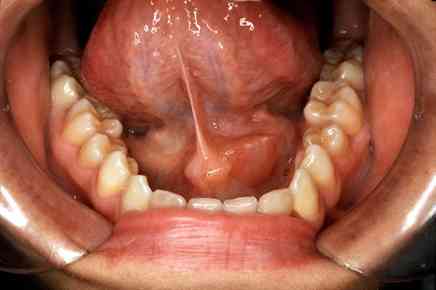

تشخيص التهاب الغدد اللعابية: الفحص السريري: يتم إجراء الفحص بالإضافة إلى الاستعلام عن التاريخ الطبي للمريض. الفحوصات المخبرية: تشمل فحوصات الدم، إذ يدل ارتفاع كريات الدم البيضاء على وجود عدوى بكتيري ... اقرأ المزيد